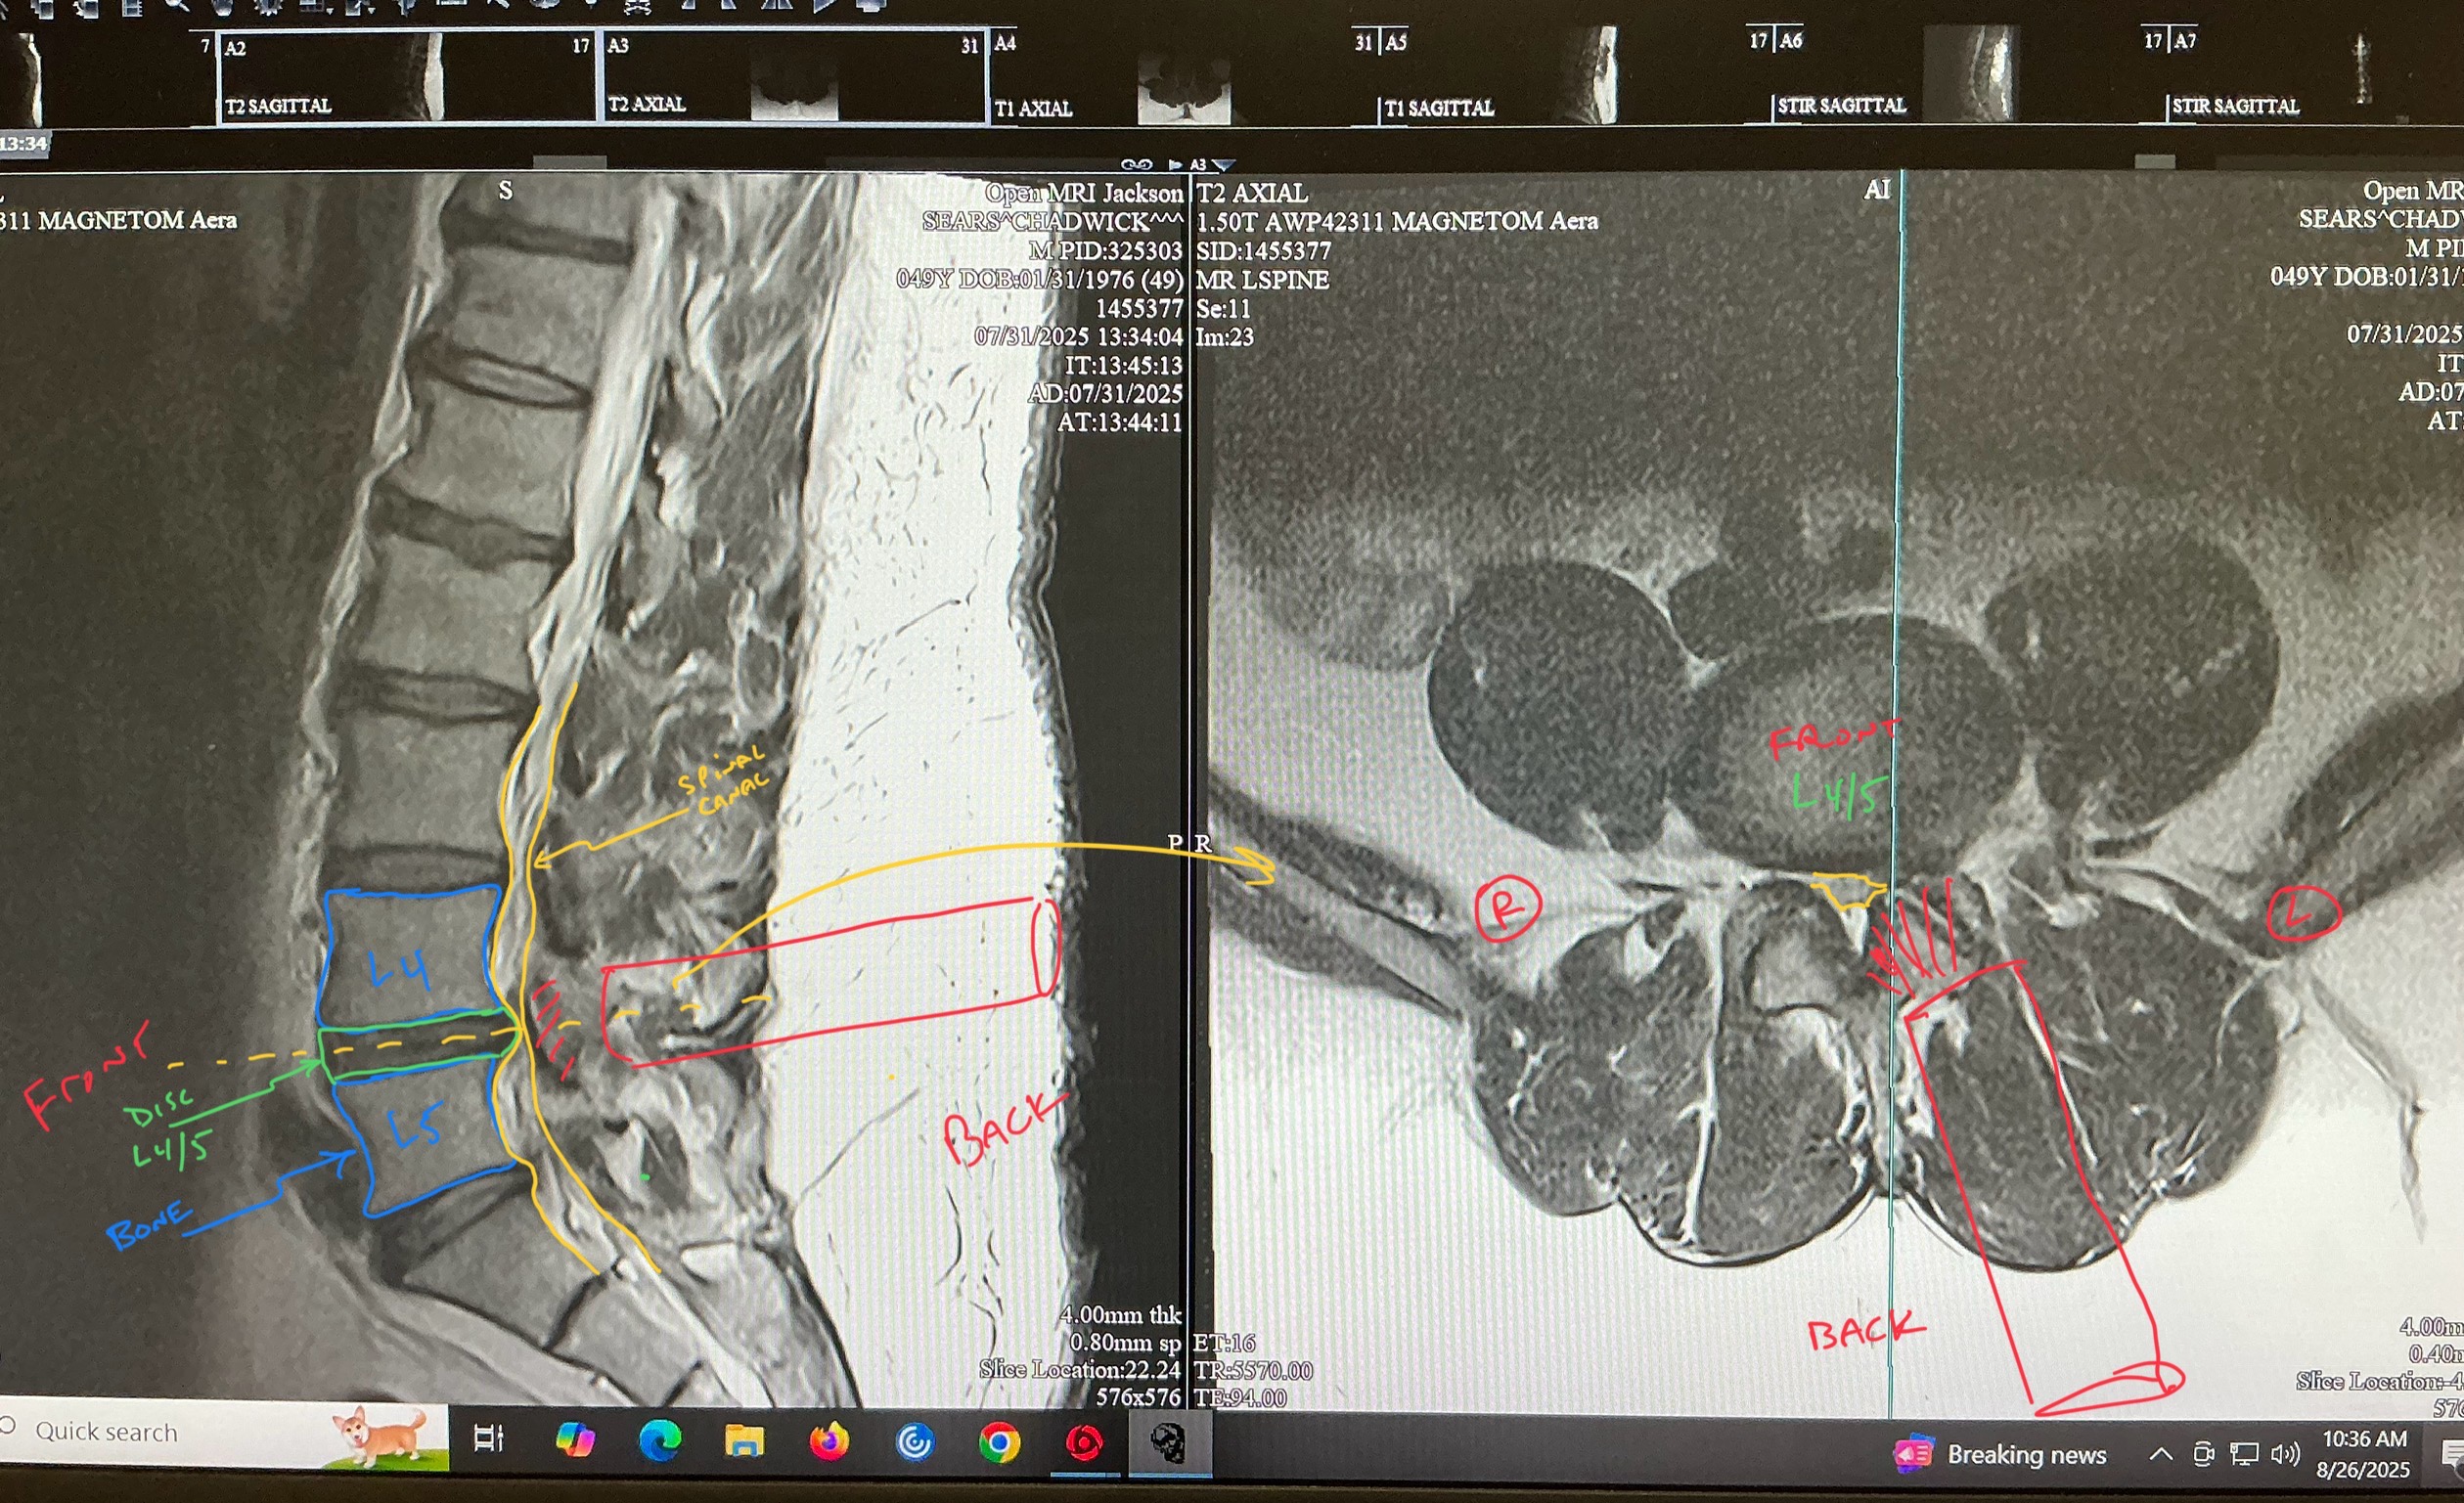

The past two years have been incredibly challenging for Chad. After a workplace injury, he underwent arm surgery that, unfortunately, didn’t go as planned. Now, he’s facing another hurdle: the need for back surgery. These medical setbacks have taken a toll, and we’re reaching out for your support to help cover the costs of his treatment and recovery.